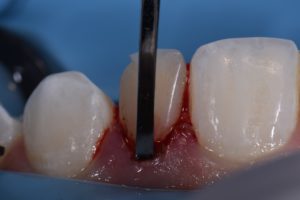

This case was referred to me for improvement of the esthetics of composite bonding on #7 and 10. A diagnostic wax-up was generated as the referring dentist required certain proportions relative to primary anatomy to be confirmed before starting. A decision was made to modify the gingival contour of 10 (diode, 810nm, 980nm, 1.0W SuperPulsed) (Gemini, Ultradent, UT), with bone sounding the basis for whether osseous recontouring was necessary. In this case, transsulcular osseous recontouring using a Wedelstaedt chisel (Kois) (Brasseler) was utilized to re-establish biologic width on the day of the restorations. Approximate full healing time: 3 months. Approximate “purple” look to gingiva: 2-3 weeks. Most of the old composite was removed except for areas where it could not easily be distinguished from tooth structure. After defining finish lines, the teeth were isolated with metal strips and micro air abraded (27 micron aluminum oxide) before a total etch approach. Silane coupling agent was utilized (GC G-MultiPrimer) before bonding (GC G-Premio Bond). A layered approach was utilized (4 separate layers) using shades XL1 Enamel, A1 Enamel, XL2 Dentin, Trans Clear from Kerr Harmonize.